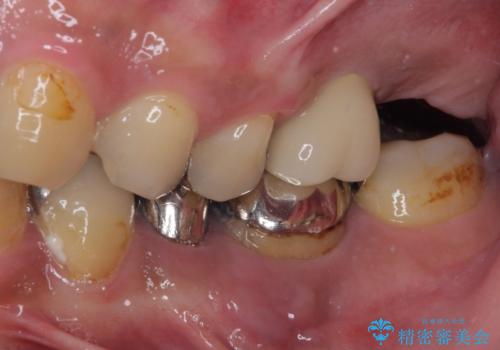

目立つ金属をすべてセラミックに 全顎的メタルフリー治療

欠損している歯や、割れてしまって抜歯の必要な歯などがあり、咬合力が強いため欠損部はインプラント補綴を前提に治療を行うこととしました。

しかしながら、左下の抜歯部位は骨欠損が著しく大きく、多大な垂直的骨造成を要するため、3歯を支台としたブリッジによる補綴治療とし、右下のみをインプラント補綴としました。

小さい修復物の銀歯が装着されている歯はセラミックインレーにて、その他はオールセラミッククラウンにて補綴治療を進めることとしました。